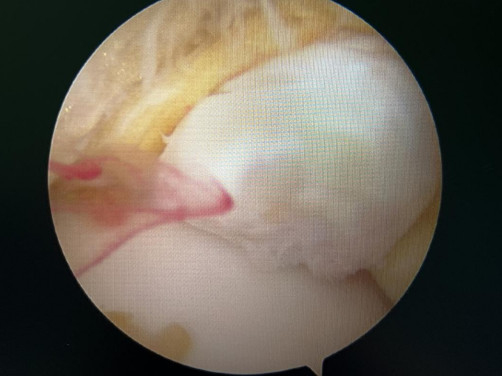

踝關(guān)節(jié)鏡見前方長骨刺

醫(yī)生們在手術(shù)中發(fā)現(xiàn),李先生的右踝關(guān)節(jié)軟骨損傷明顯,踝關(guān)節(jié)前方及內(nèi)外側(cè)均有不同程度的骨質(zhì)增生,相互撞擊引起疼痛,同時(shí)距腓前及跟腓韌帶斷裂。手術(shù)醫(yī)生利用磨鉆,小心翼翼將引起撞擊的骨刺一一去除,然后,修復(fù)了損傷的關(guān)節(jié)軟骨,最后,為他完成了距腓前和跟腓韌帶的修復(fù)。